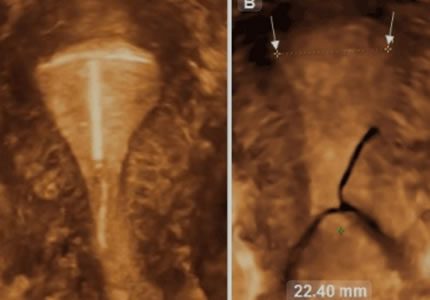

Comprehensive pelvic ultrasound evaluations for a wide range of non-pregnancy female health concerns, symptoms, or referrals.

Routine & Diagnostic Gynaecological Scans